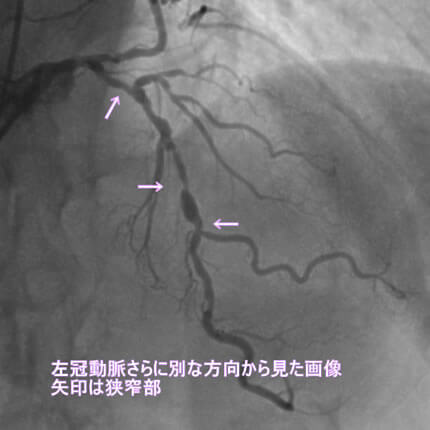

危険因子が特に複合的にあると動脈硬化は加速します。今回は、動脈硬化が加速するとどうなるか、実際の症例でお示しします。なお、お見せします画像は、すべて動画から静止画像にしています。実際には冠動脈造影は動画で見ます。

また、動脈硬化は冠動脈だけに生じる訳ではないことも示したいと思います。冠動脈に病変がある方は他の動脈にも強い動脈硬化を認めることが多いのです。具体的には腹部大動脈瘤、胸部大動脈瘤、脳梗塞、脳出血、下肢動脈閉塞などを合併します。逆にこれらの病気が見つかってそれから冠動脈疾患が見つかることも結構あります。血管は三次元構造なので色々な方向から撮影して血管形態を確かめます。同じ血管を左右上下や斜め方向から撮影します。

1番目の患者さんは80歳の男性です。この方の危険因子は高血圧、高脂血症、喫煙です。この方の冠動脈造影と腹部CT画像を示します。図1-1から1-8の画像は全て全てこの患者さんの画像です。

図1-5 左冠動脈造影像

図1-6 左冠動脈造影像

よく解らないと思いますが、冠動脈に多数の狭窄があることと冠動脈が「こぶ状変化(医学用語で瘤状変化)」を生じているのが解ると思います。